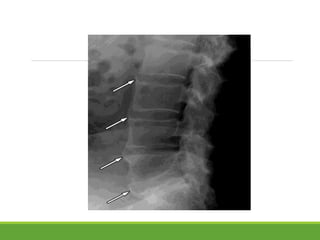

Most marked in lumbar region in the spine

loss of lordosis,

Flattening of normal anterior concavity of vertebral body leading to "squaring"

of vertebral bodies.

marginal syndesmophytes, visible on plain films as bony bridges connecting

successive vertebral bodies.

Ossification in annulus fibrosus sparing anterior longitudinal ligament and

nucleosus pulposus “bamboo spine” appearance.